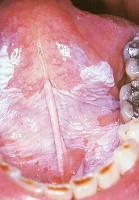

问题 白斑的好发部位是 ( )

选项 A.口底粘膜 B.软、硬腭粘膜 C.舌腹粘膜 D.颊、舌粘膜 E.唇红及唇粘膜

答案 D